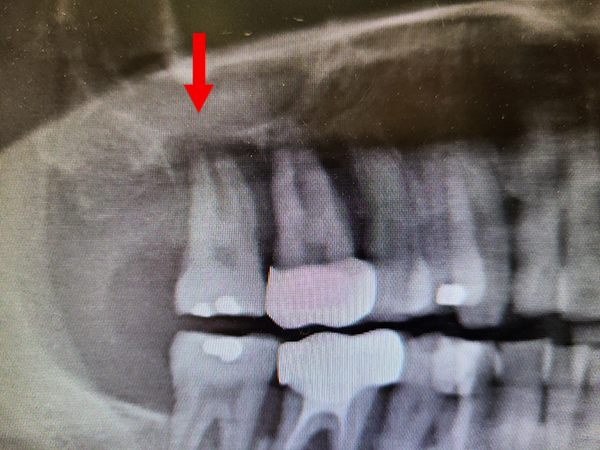

因嚴重牙周病感染造成之口腔鼻竇穿孔修補案例

術前:紅色箭頭處可見牙根周圍明顯之骨缺失,並與上顎竇貫通。

術後:經拔牙及專業工具清創後,填補膠原蛋白修補破損之上顎竇黏膜,蓋上止血敷料後縫合,術後一年可見清楚之骨再生,合併顯微鏡下牙周治療,前一顆牙齒亦得以保存。